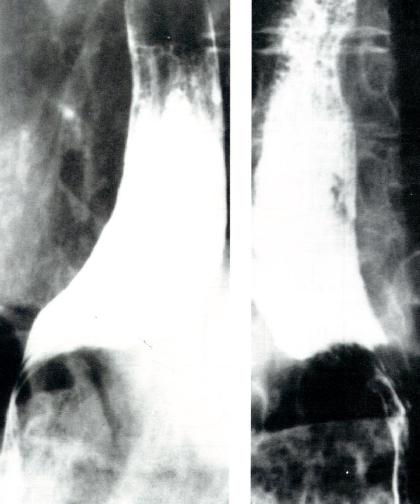

X线食管吞钡检查

食管体可呈扩张、张力低或直径正常但蠕动减少等不同的表现(图2.12)。

图2.12 硬皮病患者的吞钡表现。硬皮病X线所见可与贲

门失弛缓症相似,仅LES开口增大而不同。